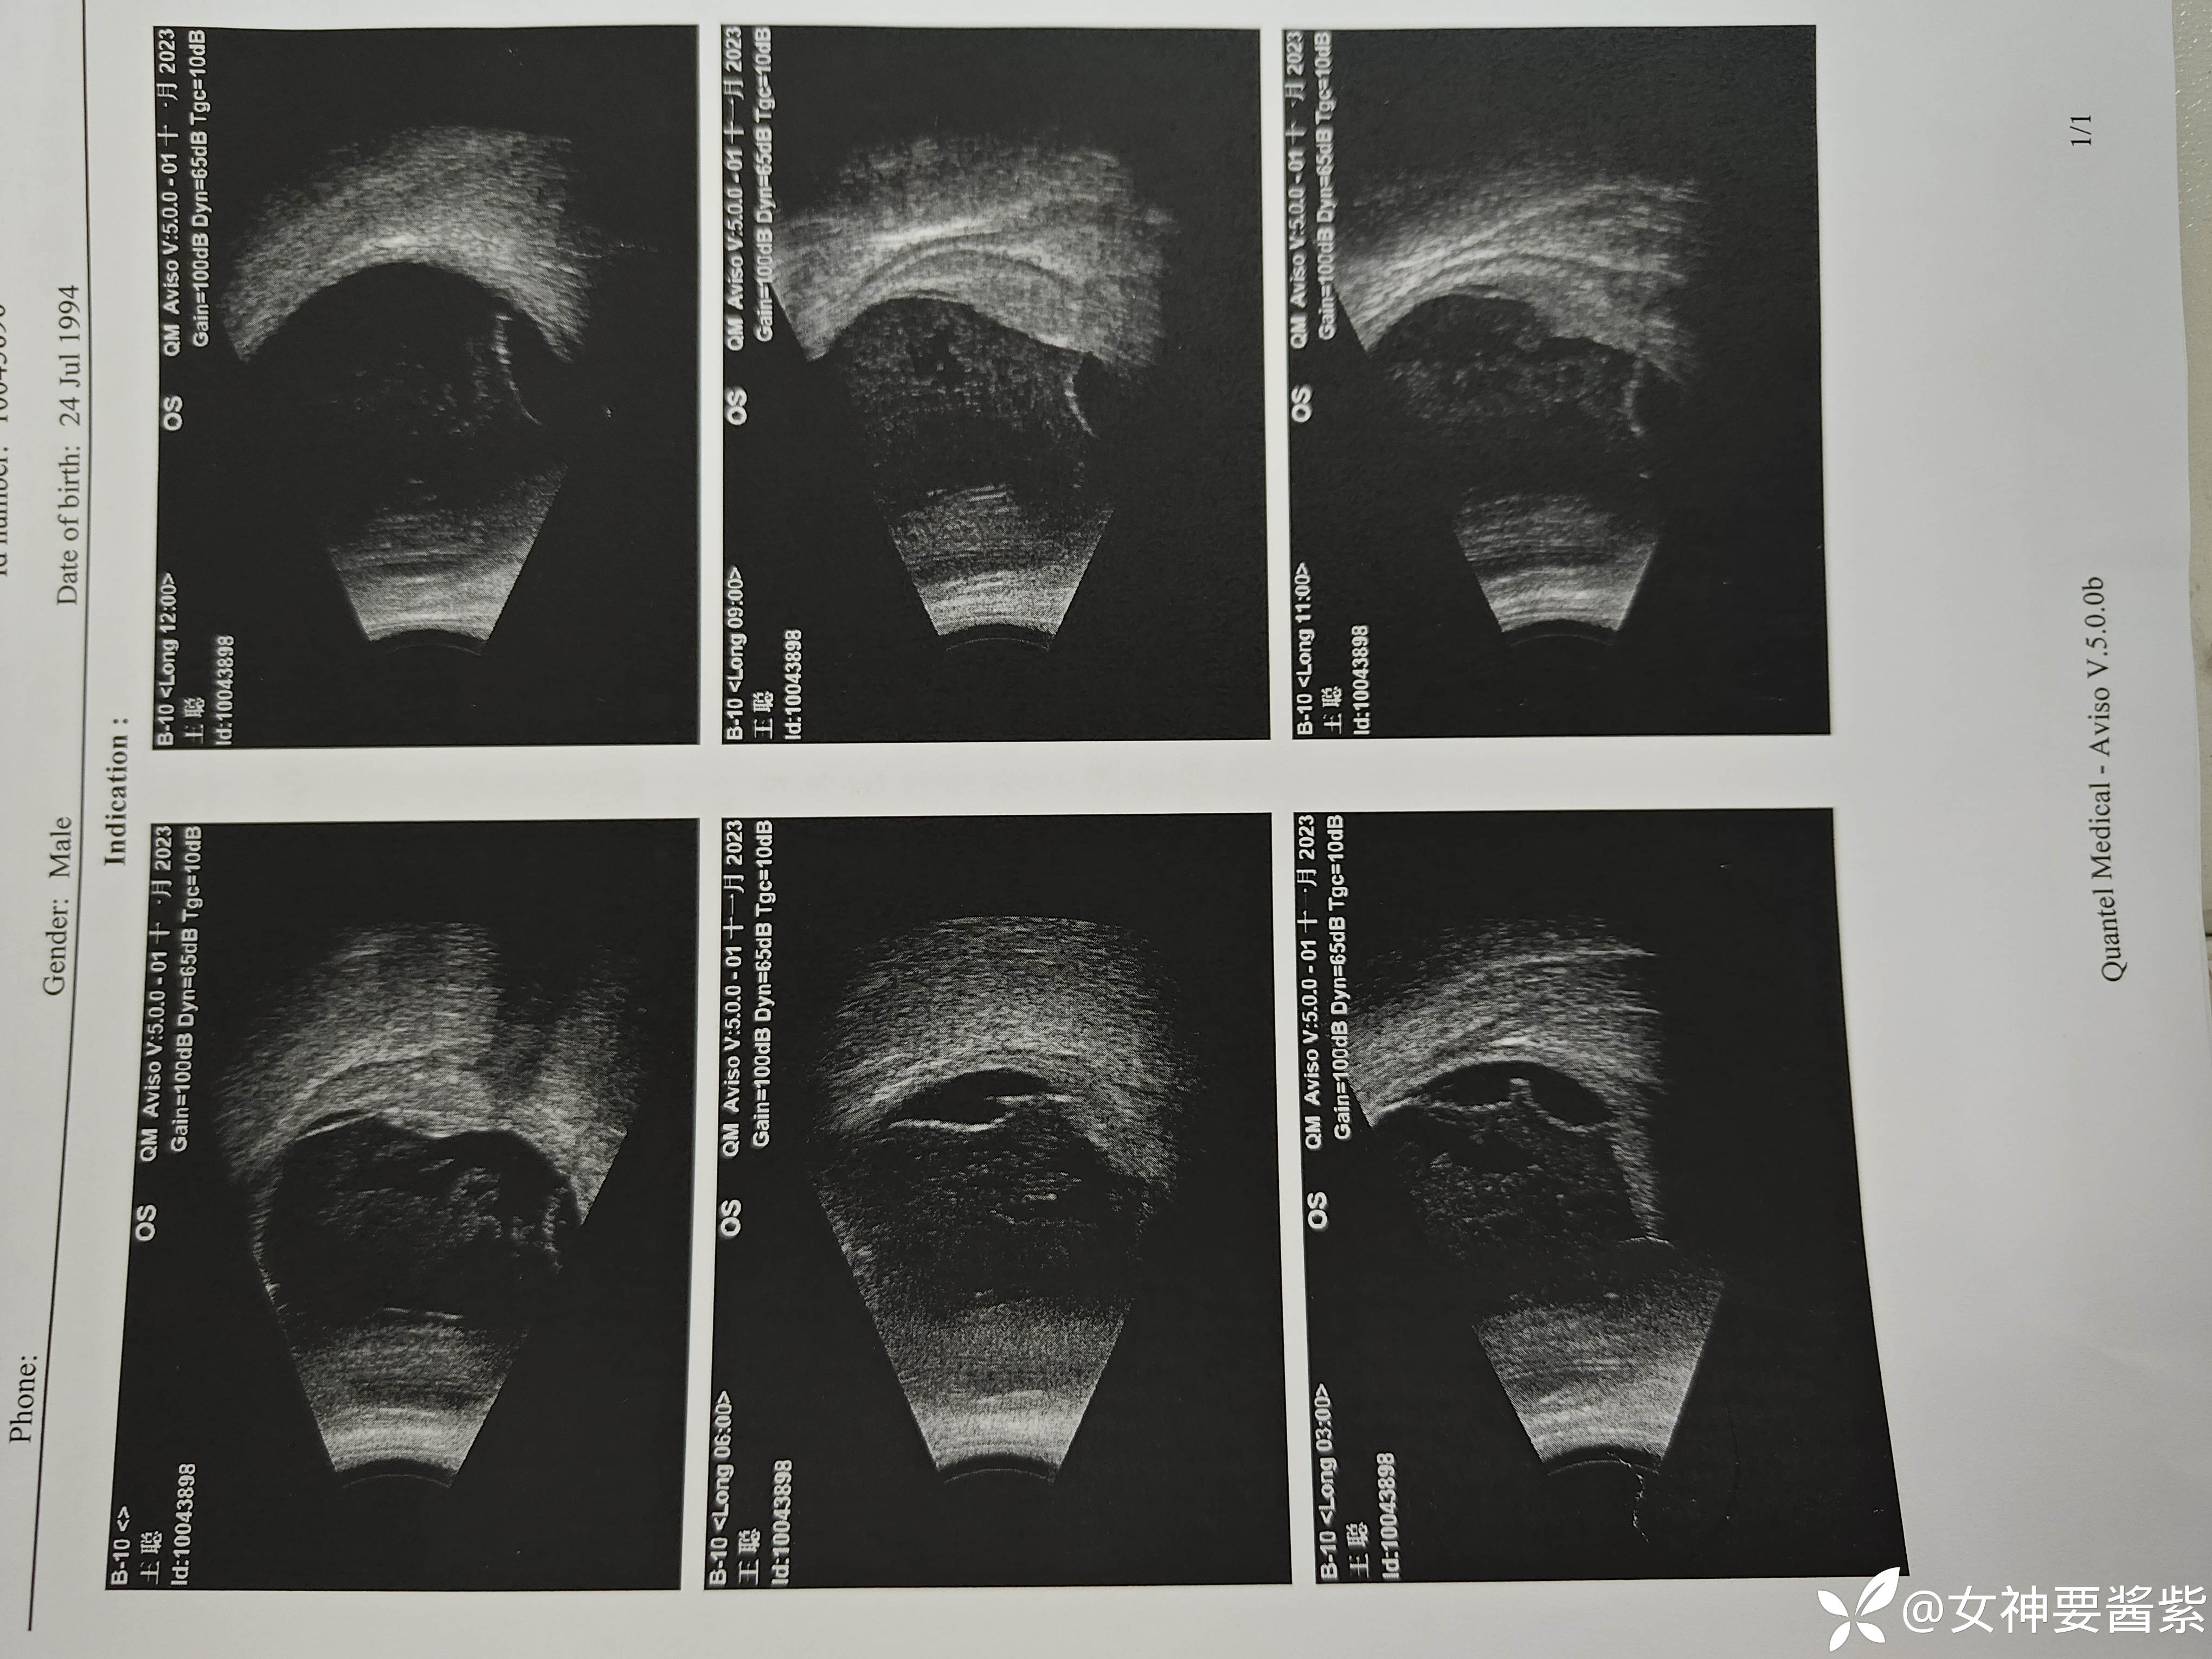

补充黑白b超和多普勒b超